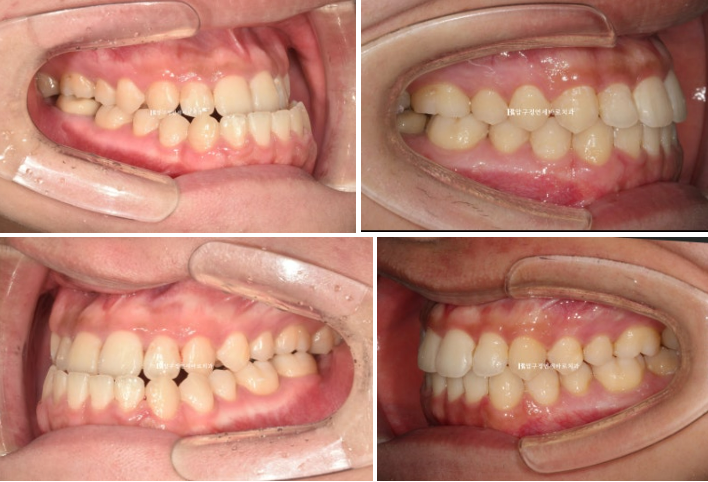

다음 사진은 구강악면외과에서 양악수술을 마친 뒤 한달간의 회복기를 가진 후 내원 시 모습입니다.

24.02

교합이 매우 좋습니다.

술전 교정도 워낙 잘 되고 구강악면외과 원장님도 수술을 잘 해주셔서

사실 술후교정으로는 별로 할 것이 없었습니다.

그래도 중심선과 좀 더 긴밀한 교합을 위해서 추가장치 제작을 합니다.

추가장치로 술후교정을 3개월부터 8월까지 약 5개월 진행했고 드디어 치료를 마무리 했습니다

23.07~24.08

중간에 수술과 회복기간, 장치제작기간을 제외하면 교정기간은 술전교정 4개월에 술후교정은 5개월 총 9개월이 걸렸습니다.

양악수술 교정 인비절라인으로 결과가 좋습니다.